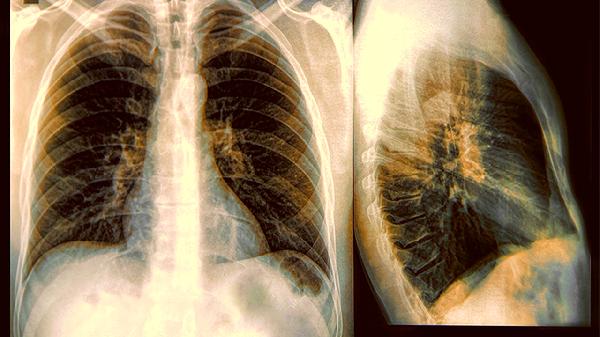

2、忽视定期体检的重要性

肺部病变早期往往没有明显症状,等出现咳嗽、胸痛时可能已错过最.佳干预期。建议40岁以上人群每年做一次低剂量CT筛查,有家族史者更应提前。